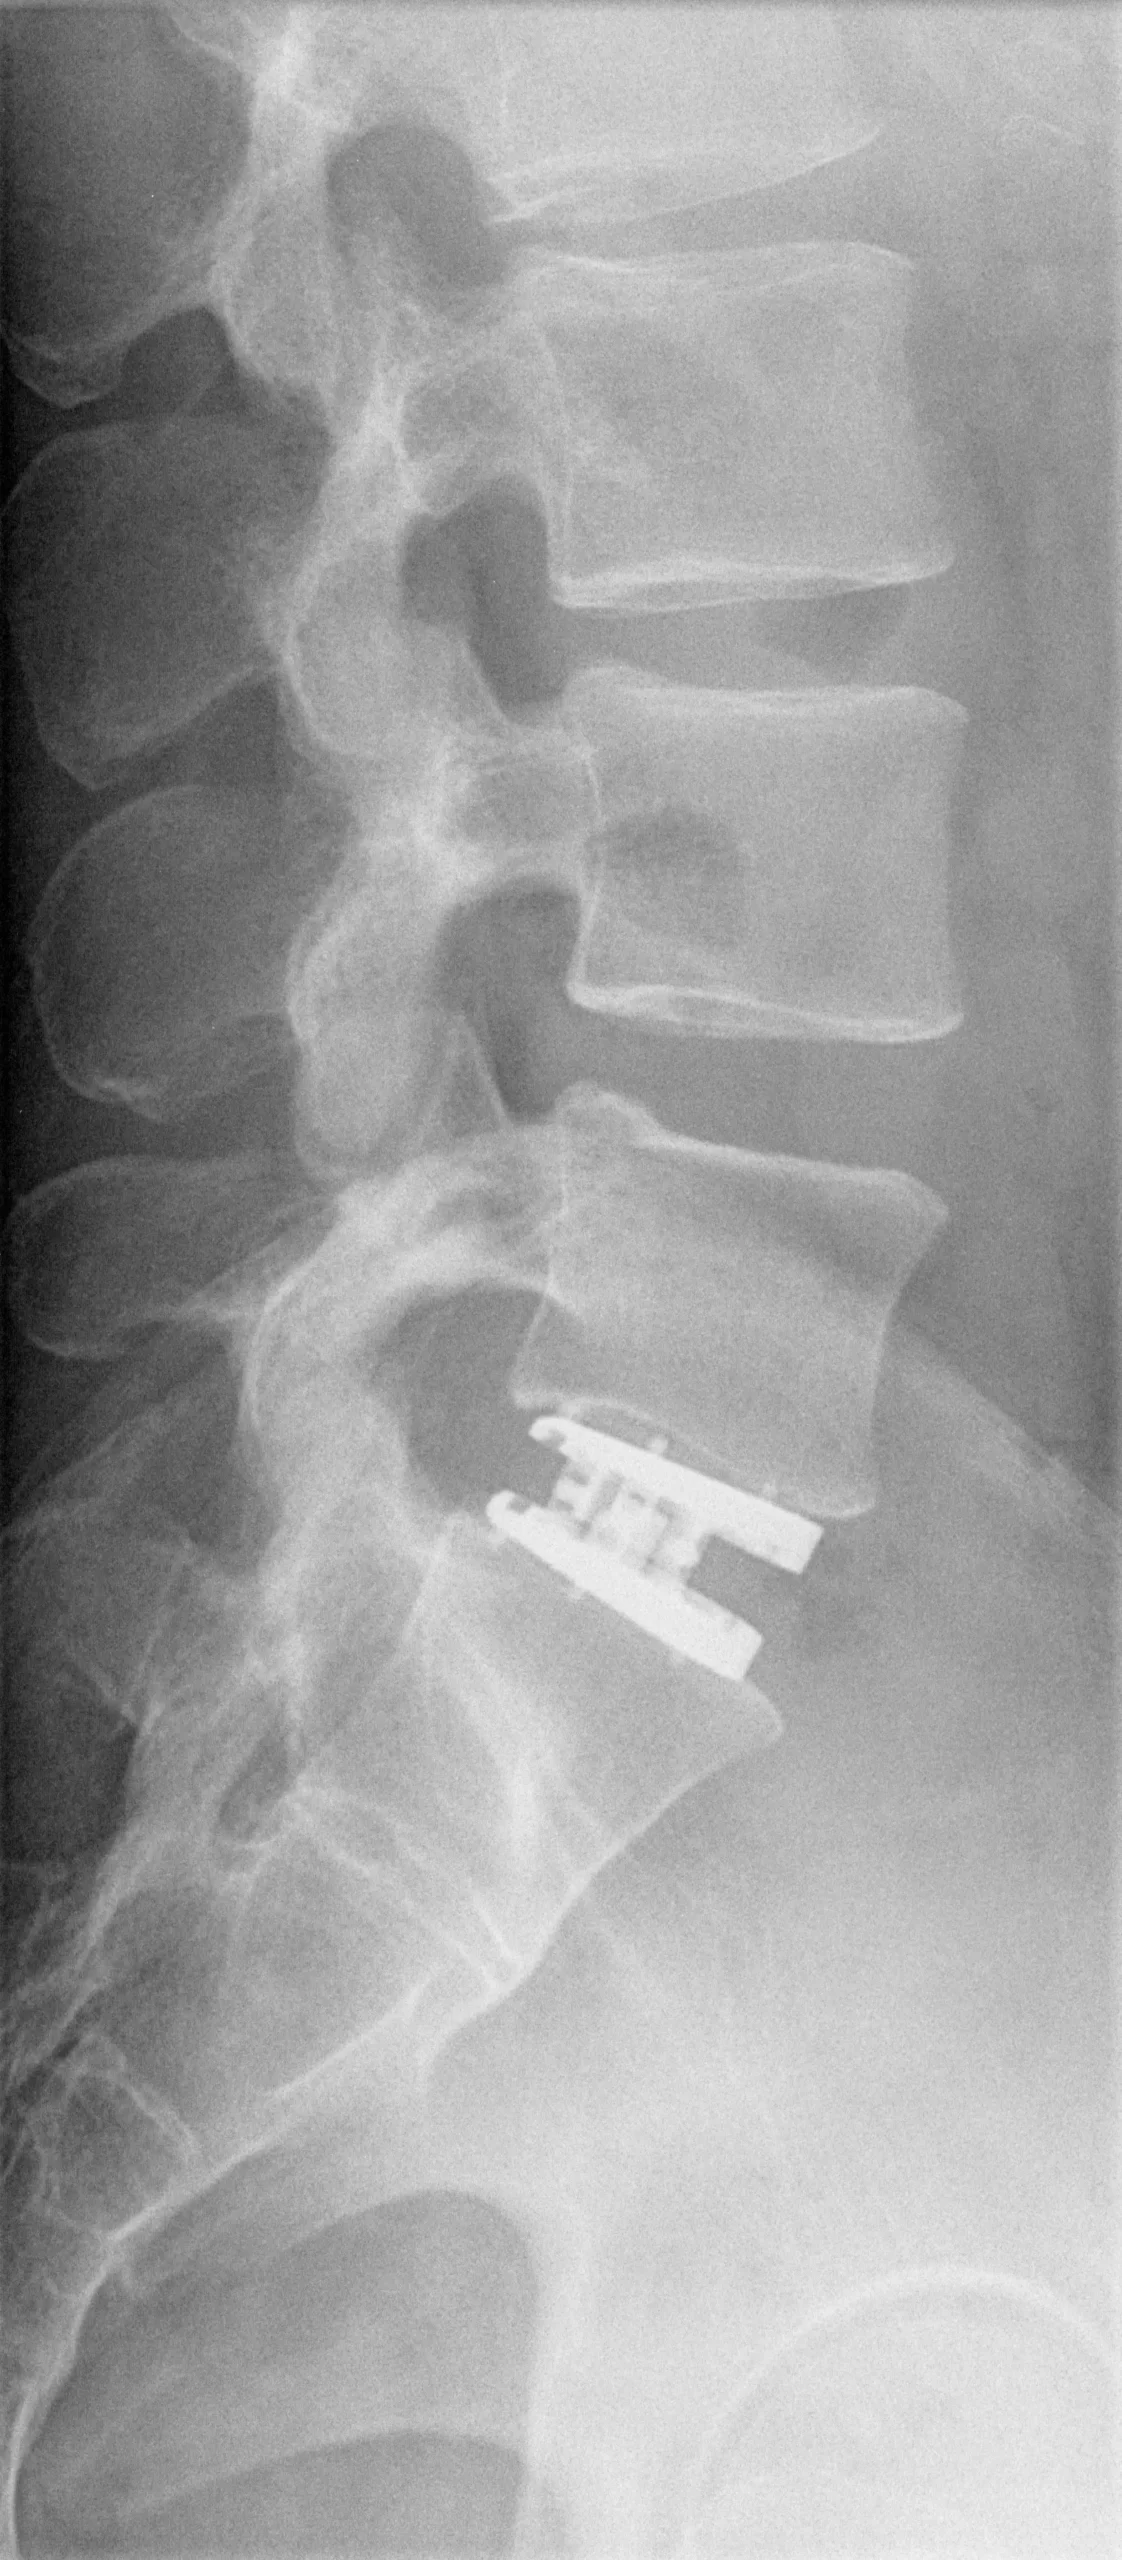

My artificial disc replacement was for my L5/S1

My artificial disc replacement was for my L5/S1. My back and disk pain was terrible. Doctors only gave me pain medication that did not fix the underlying problem. The pain and immobility got so bad that I could barely pass my physical fitness tests for work and it was difficult to travel due to having to carry large amounts of baggage.